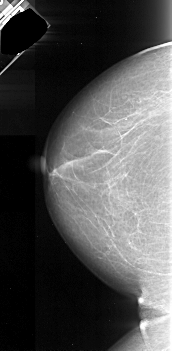

A_1048_1.RIGHT_MLO

RIGHT_MLO LINES 4846 PIXELS_PER_LINE 2506 BITS_PER_PIXEL 16 RESOLUTION 42 OVERLAY

FILE: A_1048_1.RIGHT_MLO.OVERLAY

TOTAL_ABNORMALITIES 1

ABNORMALITY 1

LESION_TYPE MASS SHAPE IRREGULAR MARGINS ILL_DEFINED

ASSESSMENT 4

SUBTLETY 5

PATHOLOGY MALIGNANT